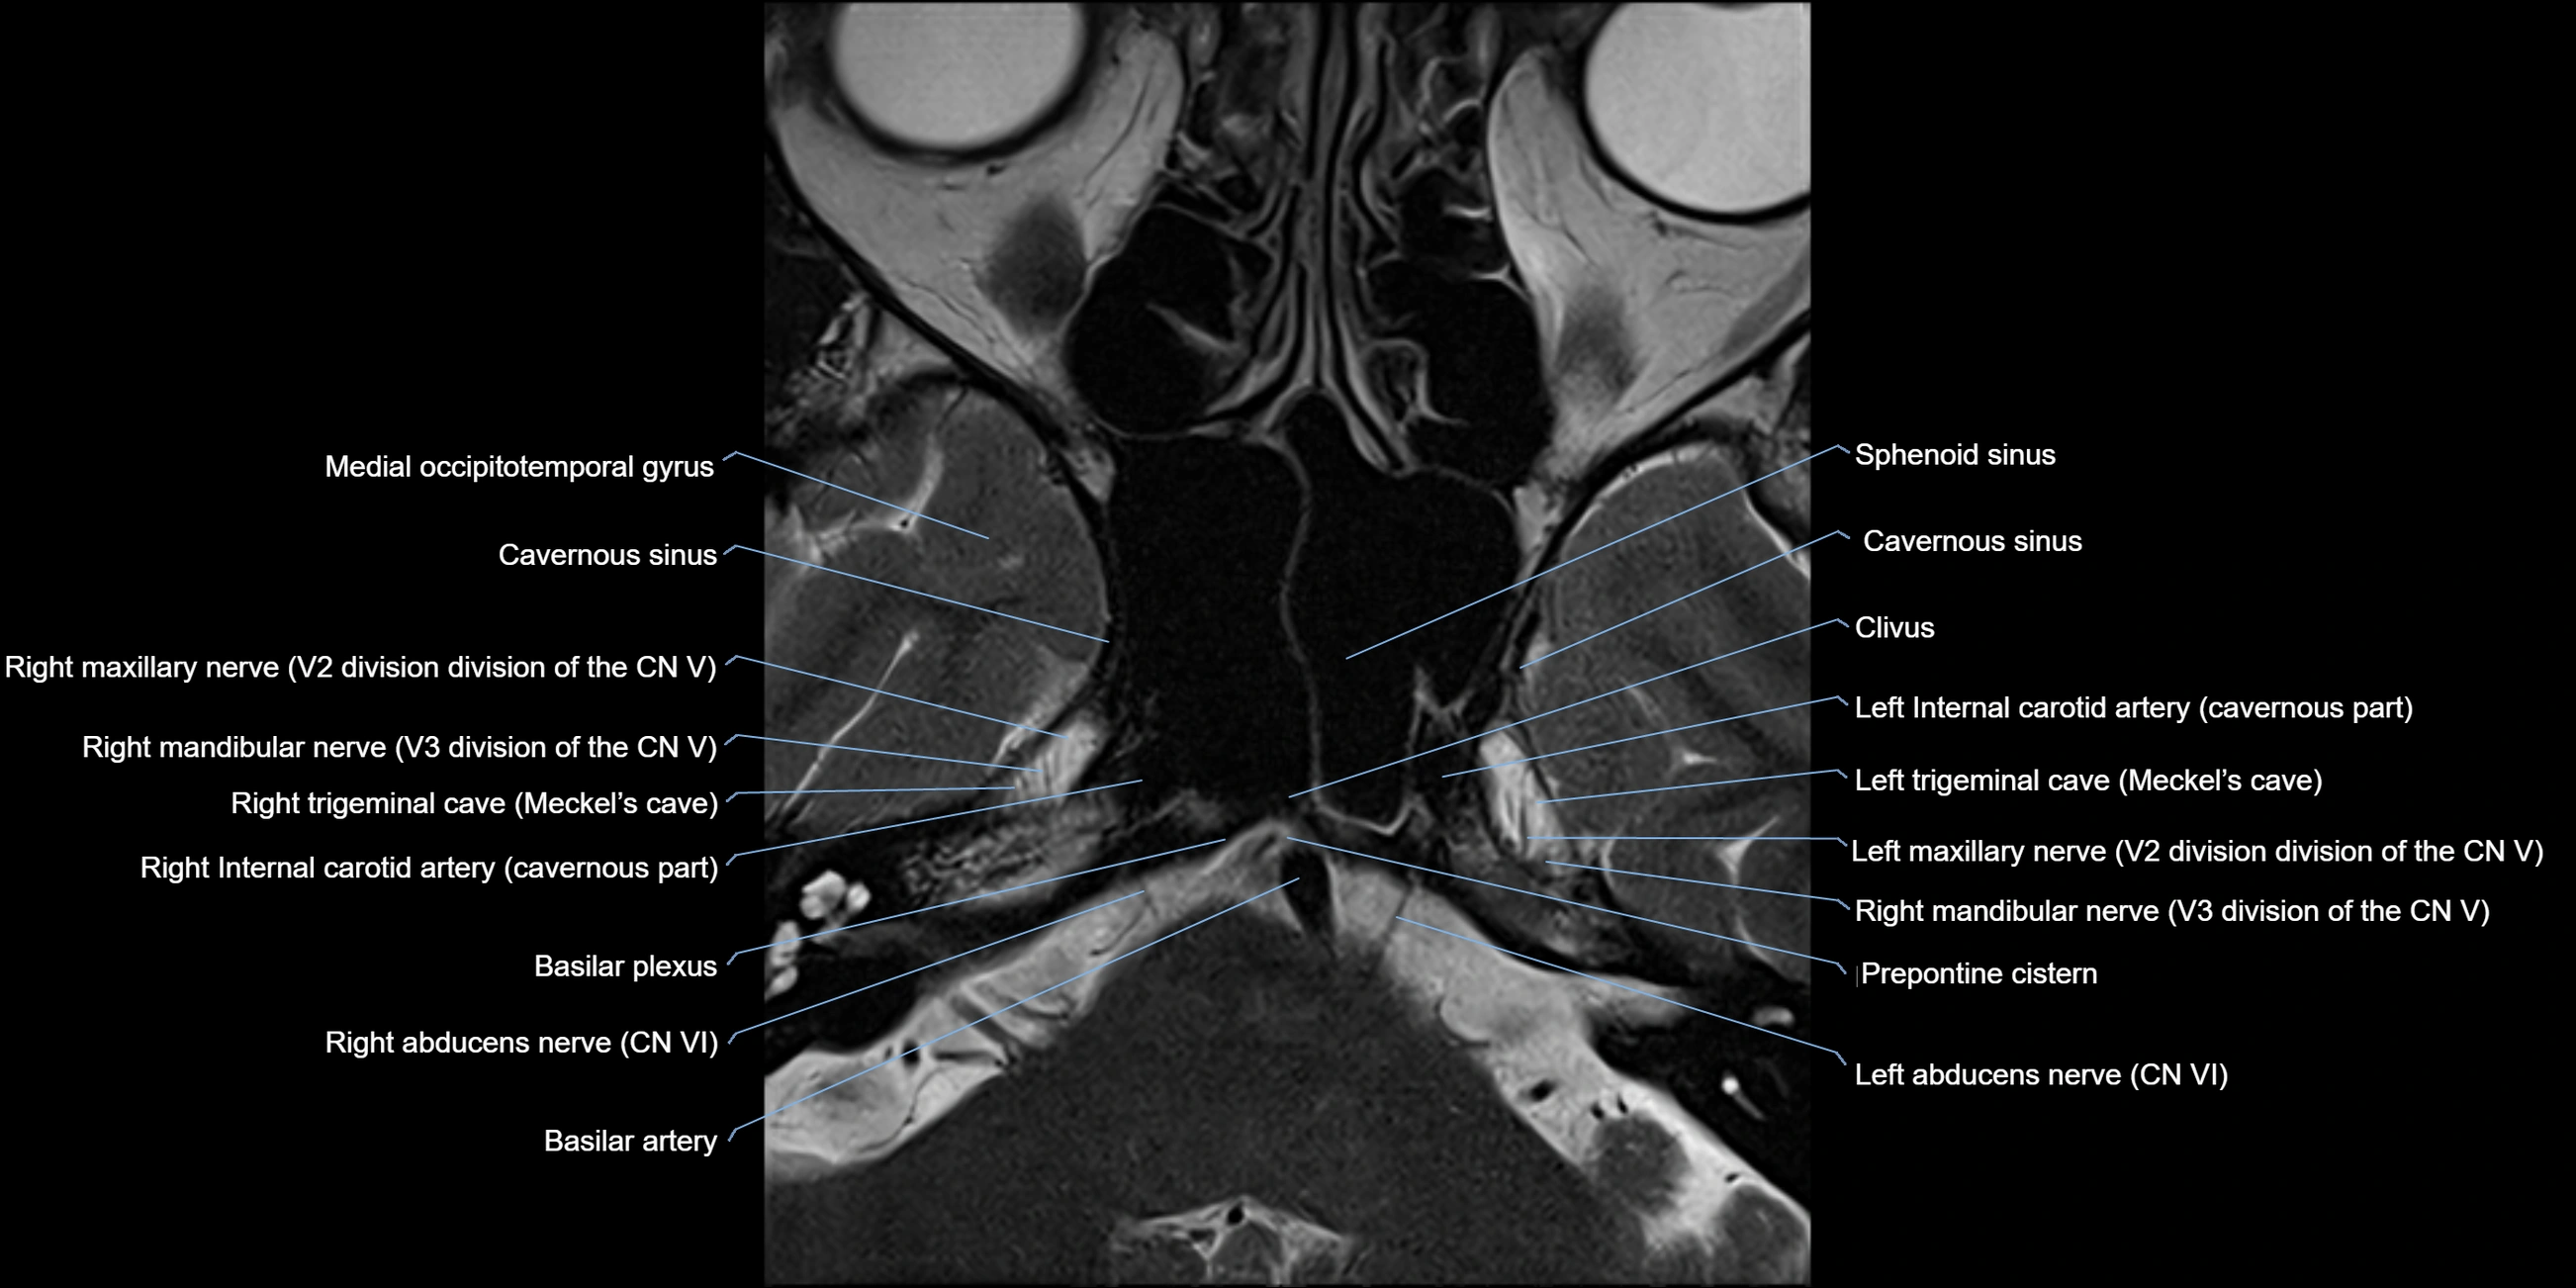

MRI Appearance

The abducens nerve is a small, thin, linear structure

Best visualized on high-resolution T2-weighted 3D MRI sequences (e.g., FIESTA or CISS)

Seen as a hypointense (dark) line running from the brainstem at the pontomedullary junction, traversing the prepontine cistern, and entering Dorello’s canal under the petrosphenoidal ligament, then into the cavernous sinus, and finally the orbit

May be challenging to visualize in standard MRI due to its small size

Pathology may be inferred by absence, displacement, or enhancement of the nerve

MRI images